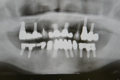

上顎全額的インプラント症例

上の全ての歯がぐらぐらな状態で左上の歯(写真向かって右上)が痛いとご来院。入れ歯は絶対に嫌ということで、まずは痛む左上(レントゲンでは右上)を抜歯、サイナスリフト(骨の移植)を併用しインプラント埋入して残りの歯で無理やり仮歯を支える。左上インプラントが生着し左で咬めるようになったら前歯(鼻の下がくぼんで老人様顔貌を避けるため骨の厚みを出す手術併用)、右上の歯はすべて抜歯して(ソケットリフト併用)しインプラント埋入。生着に時間のかかる日本承認の従来型のインプラントだったので計1年以上の治療期間を要しましたが一度もご自身の歯で咬めない時期はないようにしました。